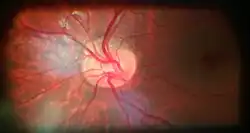

![]() Ophthalmoscopy photograph showing the optic disc as a bright area on the right where blood vessels converge.  | |

The optic disc or optic nerve head is the point of exit for ganglion cell axons leaving the eye. Because there are no rods or cones overlying the optic disc, it corresponds to a small blind spot in each eye.

The ganglion cell axons form the optic nerve after they leave the eye. The optic disc represents the beginning of the optic nerve and is the point where the axons of retinal ganglion cells come together. The optic disc in a normal human eye carries 1–1.2 million afferent nerve fibers from the eye toward the brain. The optic disc is also the entry point for the major arteries that supply the retina with blood, and the exit point for the veins from the retina.[1]

Almost all eye structures can be examined with appropriate optical equipment and lenses. Using a modern direct ophthalmoscope gives a view of the optic disc using the principle of reversibility of light. A slit lamp biomicroscopic examination along with an appropriate aspheric focusing lens (+66D, +78D or +90D) is required for a detailed stereoscopic view of the optic disc and structures inside the eye.

A biomicroscopic exam can indicate the health of the optic nerve. In particular, the eye care physician notes the colour, cupping size (as a cup-to-disc ratio), sharpness of edge, swelling, hemorrhages, notching in the optic disc and any other unusual anomalies. It is useful for finding evidence corroborating the diagnosis of glaucoma and other optic neuropathies, optic neuritis, anterior ischemic optic neuropathy or papilledema (i.e. optic disc swelling produced by raised intracranial pressure), and optic disc drusen.